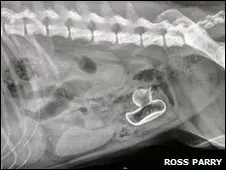

Imagem do raio X de Spike mostra o pato de borracha retirado com a cirurgia. (Foto: BBC Brasil)

Apenas depois de um exame de raio X os médicos e os tutores do cão puderam ver que o problema era um pato de borracha, que poderia ser visto com clareza no intestino do animal.